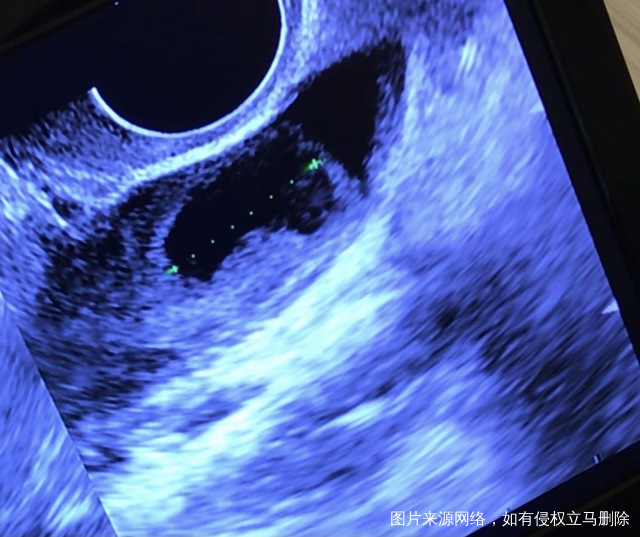

这个月没促排,b超监测说是卵泡已排,内膜10.1毫米,为什么卵泡没有消失还有17毫米留在那里?已上传照片,这是排了吗?另外,排了卵可以吃补佳乐和地屈孕酮吗?排卵后吃补佳乐主要是干什么的?